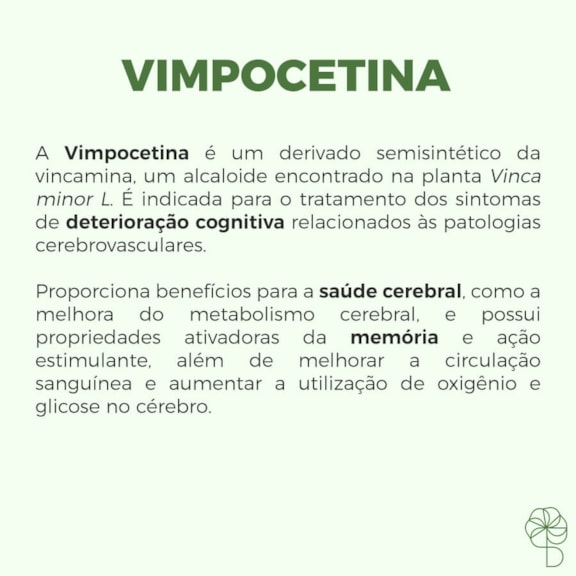

Vinpocetina: O Que É e Para Que Serve?

A vinpocetina é uma substância fascinante, derivada da vincamina, um alcaloide encontrado na pervinca. Ela tem ganhado destaque no universo da saúde cerebral por sua atuação na melhora da circulação sanguínea e nas funções cognitivas. Pense nela como uma aliada para manter seu cérebro funcionando a todo vapor.

Seu uso é voltado para quem busca otimizar o desempenho mental, auxiliando em quadros de dificuldades de memória, concentração e até mesmo em situações de menor fluxo sanguíneo para o cérebro. É um composto que desperta interesse tanto para uso terapêutico quanto como suplemento para quem deseja um suporte extra para a saúde cerebral.

Para que serve a Vinpocetina?

A principal utilidade da vinpocetina reside na sua capacidade de atuar positivamente sobre a circulação cerebral e as funções cognitivas. Ela é frequentemente indicada para auxiliar em situações onde há uma redução do fluxo sanguíneo para o cérebro, o que pode comprometer o desempenho mental. Seu uso visa melhorar a oxigenação e o aporte de nutrientes para as células cerebrais.

Além disso, a vinpocetina é conhecida por seus efeitos no suporte à memória, concentração e aprendizado. Ela atua como um agente que pode ajudar a otimizar a atividade neural, tornando o cérebro mais eficiente em seus processos. Por isso, é vista como uma ferramenta valiosa para quem busca manter a clareza mental e o vigor cognitivo.

Vinpocetina para Deterioração Cognitiva

Em casos de deterioração cognitiva, especialmente aquela relacionada ao envelhecimento ou a condições vasculares, a vinpocetina pode ser uma aliada importante. Ela atua melhorando o metabolismo cerebral e o fluxo sanguíneo, o que é fundamental para nutrir as células nervosas e manter suas funções vitais.

A substância ajuda a combater os efeitos negativos da redução do fluxo sanguíneo, que muitas vezes é a causa subjacente da perda de memória e da dificuldade de concentração. Ao otimizar o ambiente cerebral, a vinpocetina contribui para a preservação das funções cognitivas.